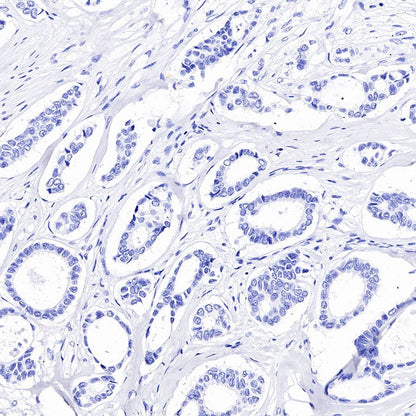

IHC shows positive staining in paraffin-embedded human colon cancer. Anti-GPA33 antibody was used at 1/2000 dilution, followed by a HRP Polymer for Mouse & Rabbit IgG (ready to use). Counterstained with hematoxylin. Heat mediated antigen retrieval with Tris/EDTA buffer pH9.0 was performed before commencing with IHC staining protocol.